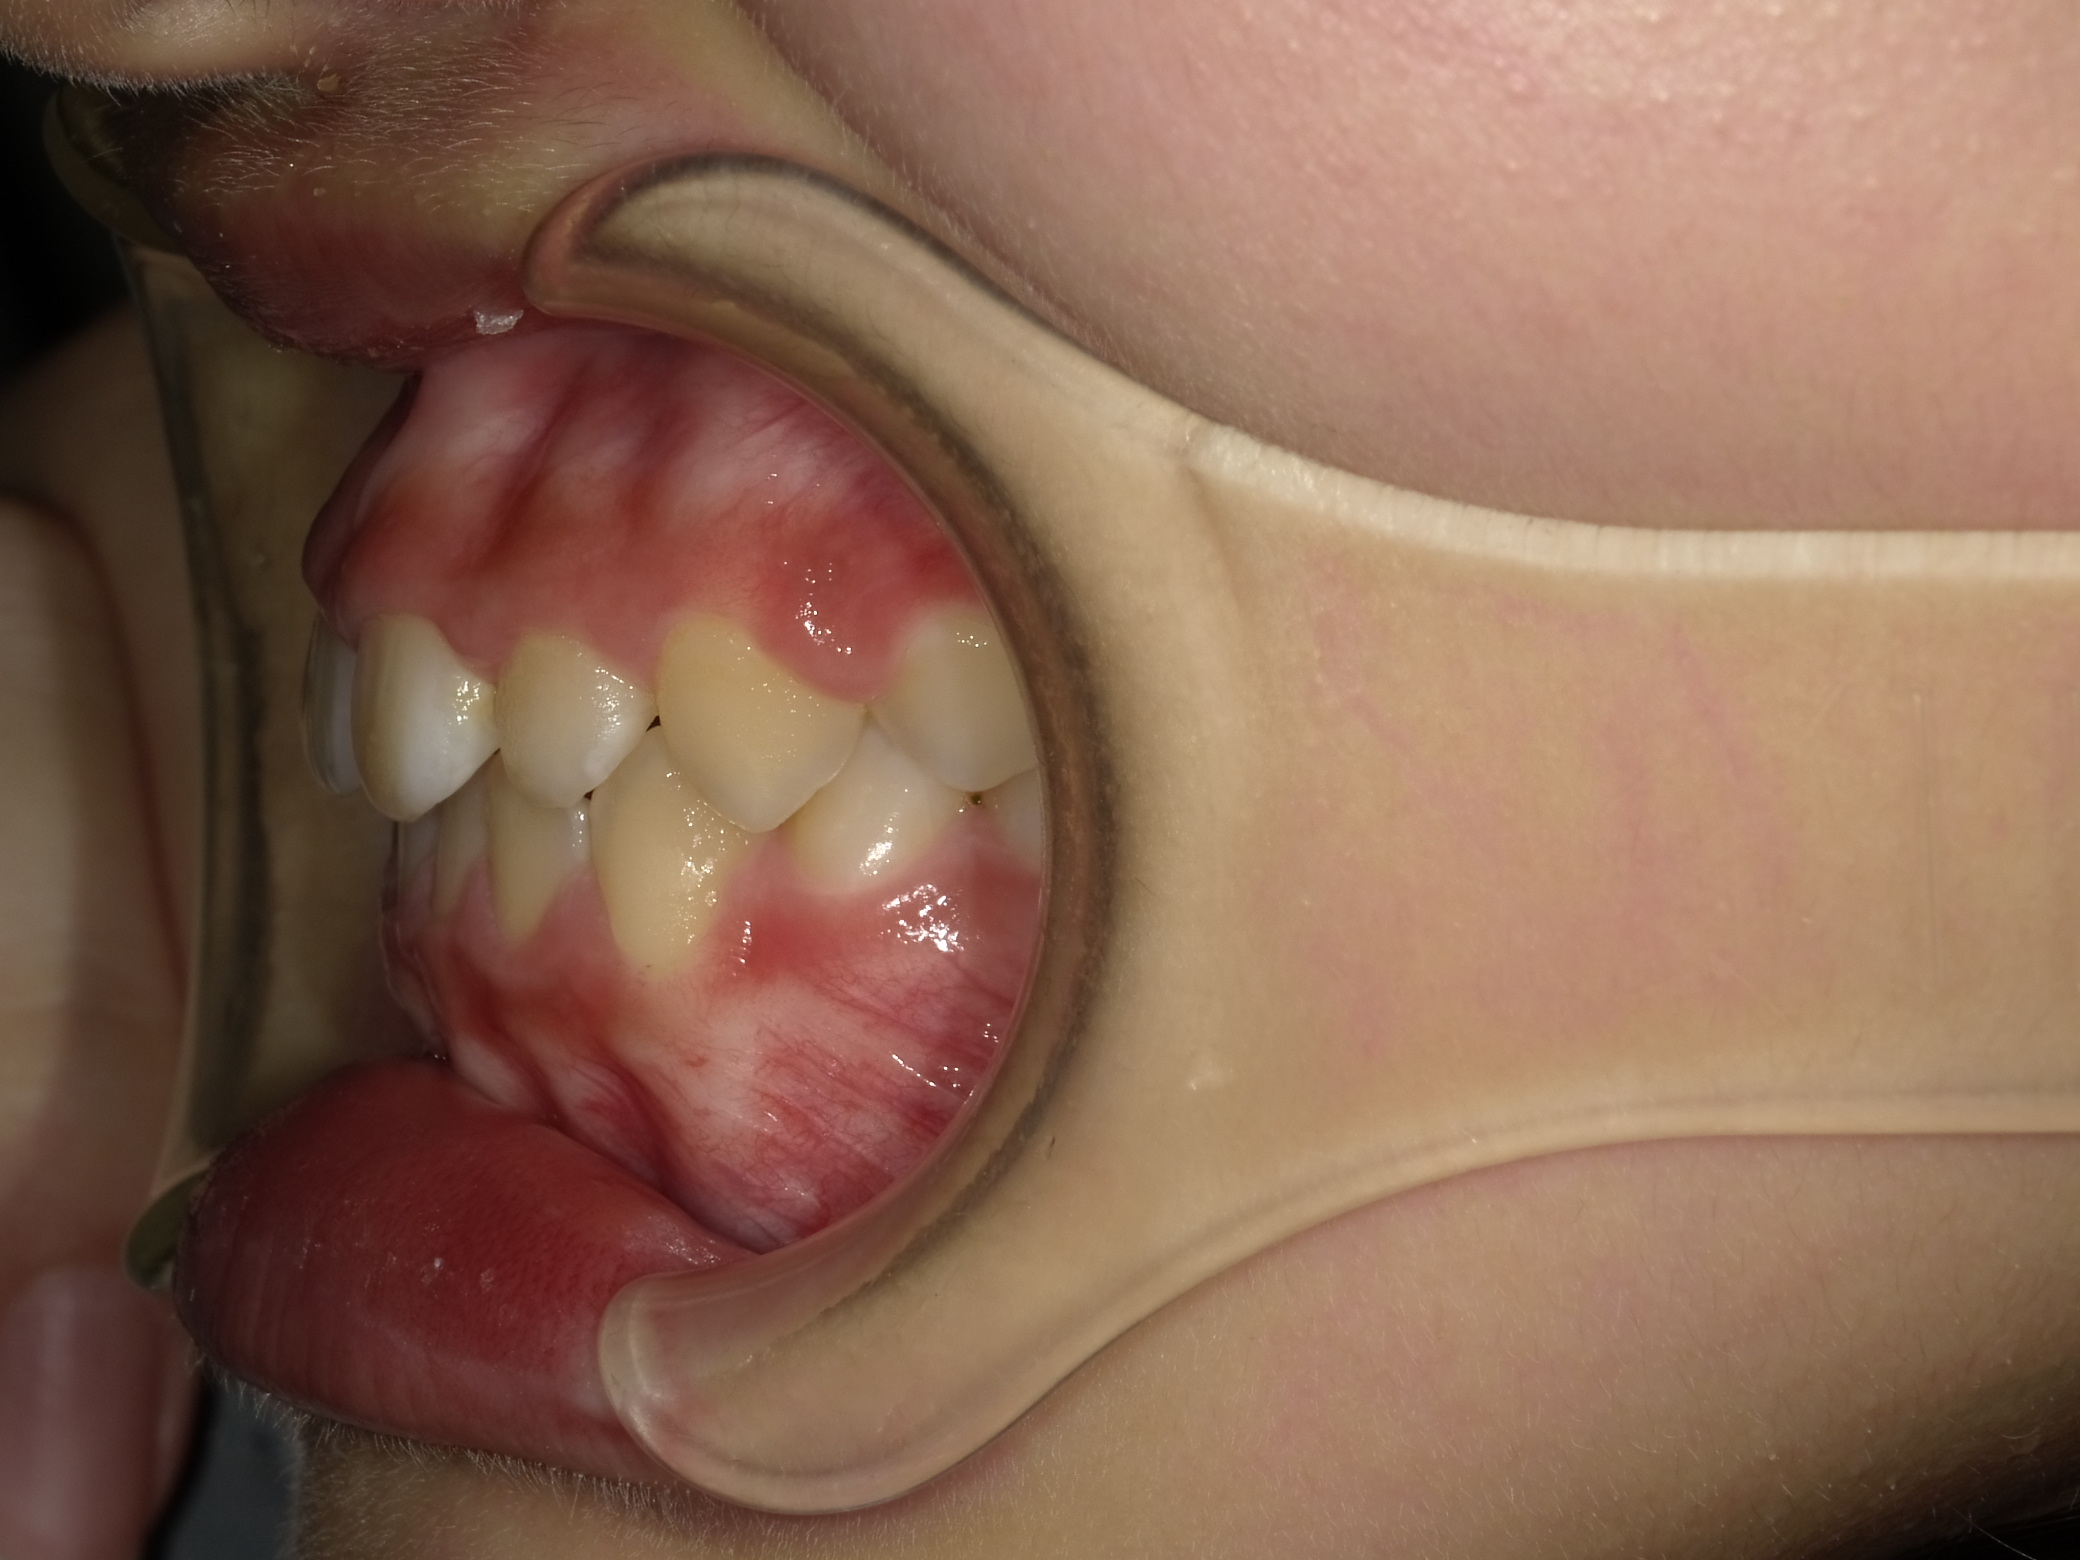

左横